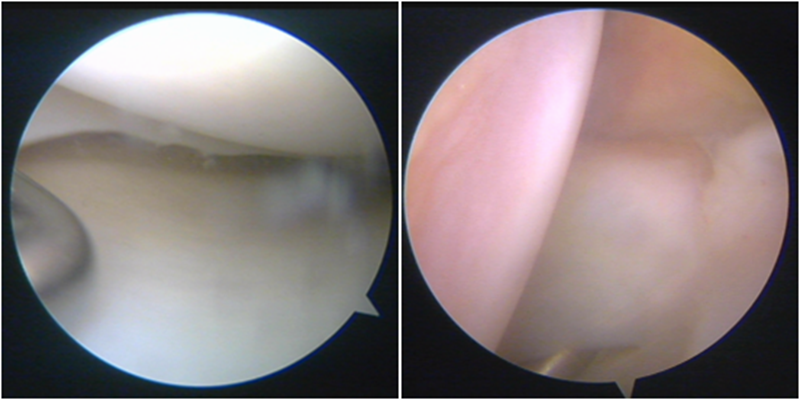

股骨侧保残骨道建立

股骨侧骨道建立,椭圆形扩孔保残9mm